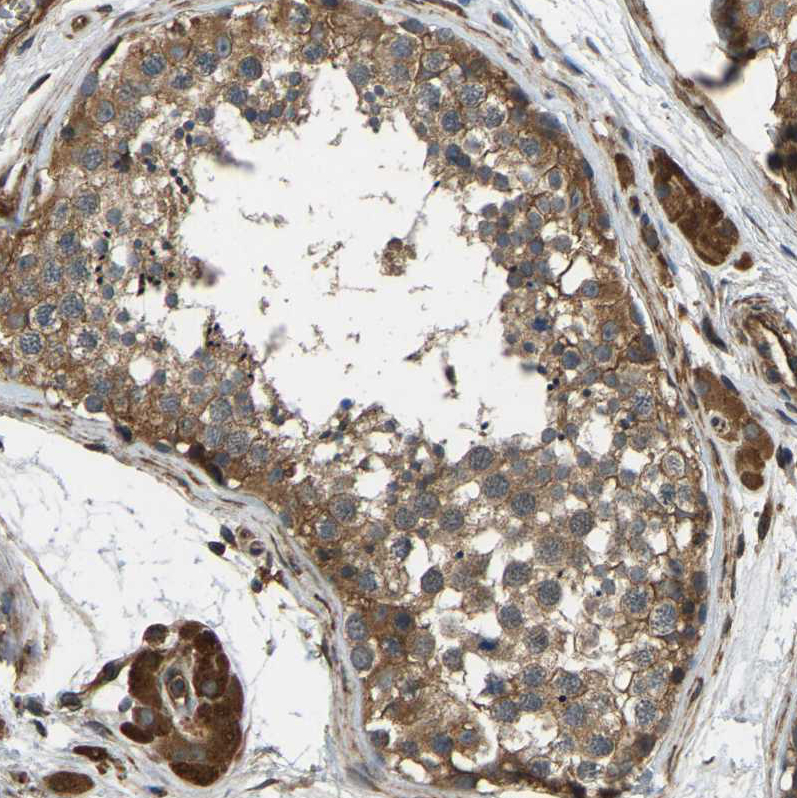

Immunohistochemical staining of human cerebral cortex, liver, prostate and testis using Anti-ERGIC1 antibody HPA018900 (A) shows similar protein distribution across tissues to independent antibody HPA018666 (B).